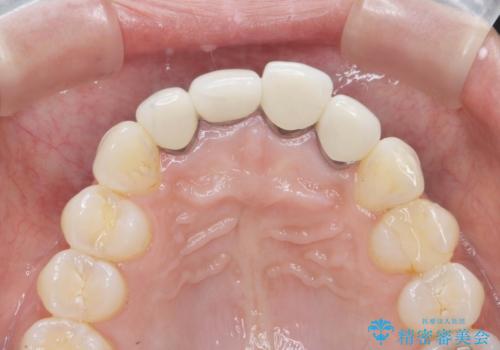

金属色の見える前歯 オールセラミックで審美治療

- 前歯のクラウンの見た目が不自然、歯の根元が見えたり金属色が気になるので改善したい、とセラミック治療を希望され来院されました。

歯肉の位置変化による審美障害を改善するため、オールセラミックジルコニアクラウンで再治療を行い審美性の改善を計画します。

見た目が自然になり、色調も天然の歯とおなじような透明感のある色調が再現され、大変喜んでいただくことができました。